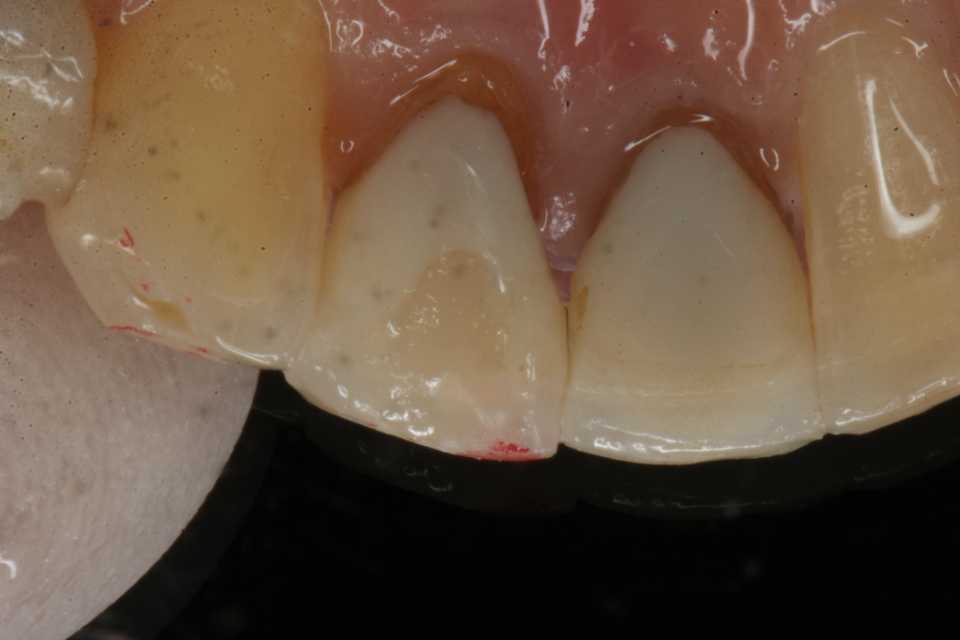

CRで充填する。今のところ​CR+ボンディング材​が最も辺縁封鎖性に優れている。

信じられないだろうが、3MIX+α-TCPを根管充填材の上に置くだけで治る。